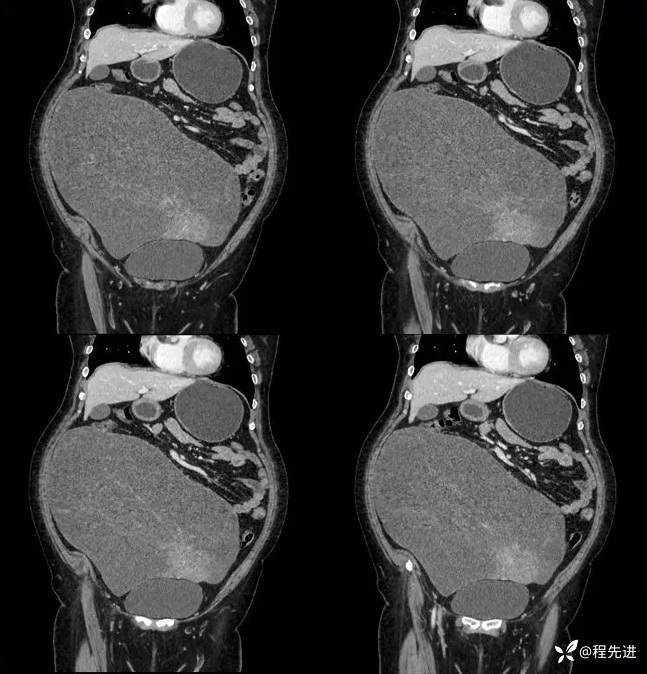

门脉期:

延迟期: